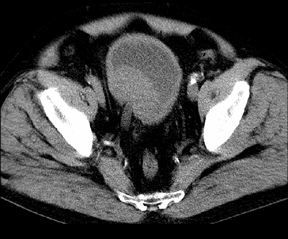

РКТ в диагностике РМП сравнима по эффективности с УЗКТ. Диагностическая точность обоих методов составляет около 60%, поэтому РКТ нашла ограниченное применение и используется главным образом для выявления экстравезикального распространения опухоли и уточнения состояния регионарных лимфатических узлов (рис. 4). Для повышения диагностических возможностей РКТ в мочевой пузырь пробовали вводить газ, рентгеноконтрастные вещества, жировые эмульсии, но эти мероприятия не привели к расширению диагностических возможностей метода. По литературным данным, точность стадирования РМП с помощью РКТ колеблется от 60 до 80%.

Рисунок 4. На КТ-снимке органов таза отчетливо определяется опухоль на задне-правой стенке мочевого пузыря с инвазией правого мочеточника. Забрюшинные лимфатические узлы не увеличены